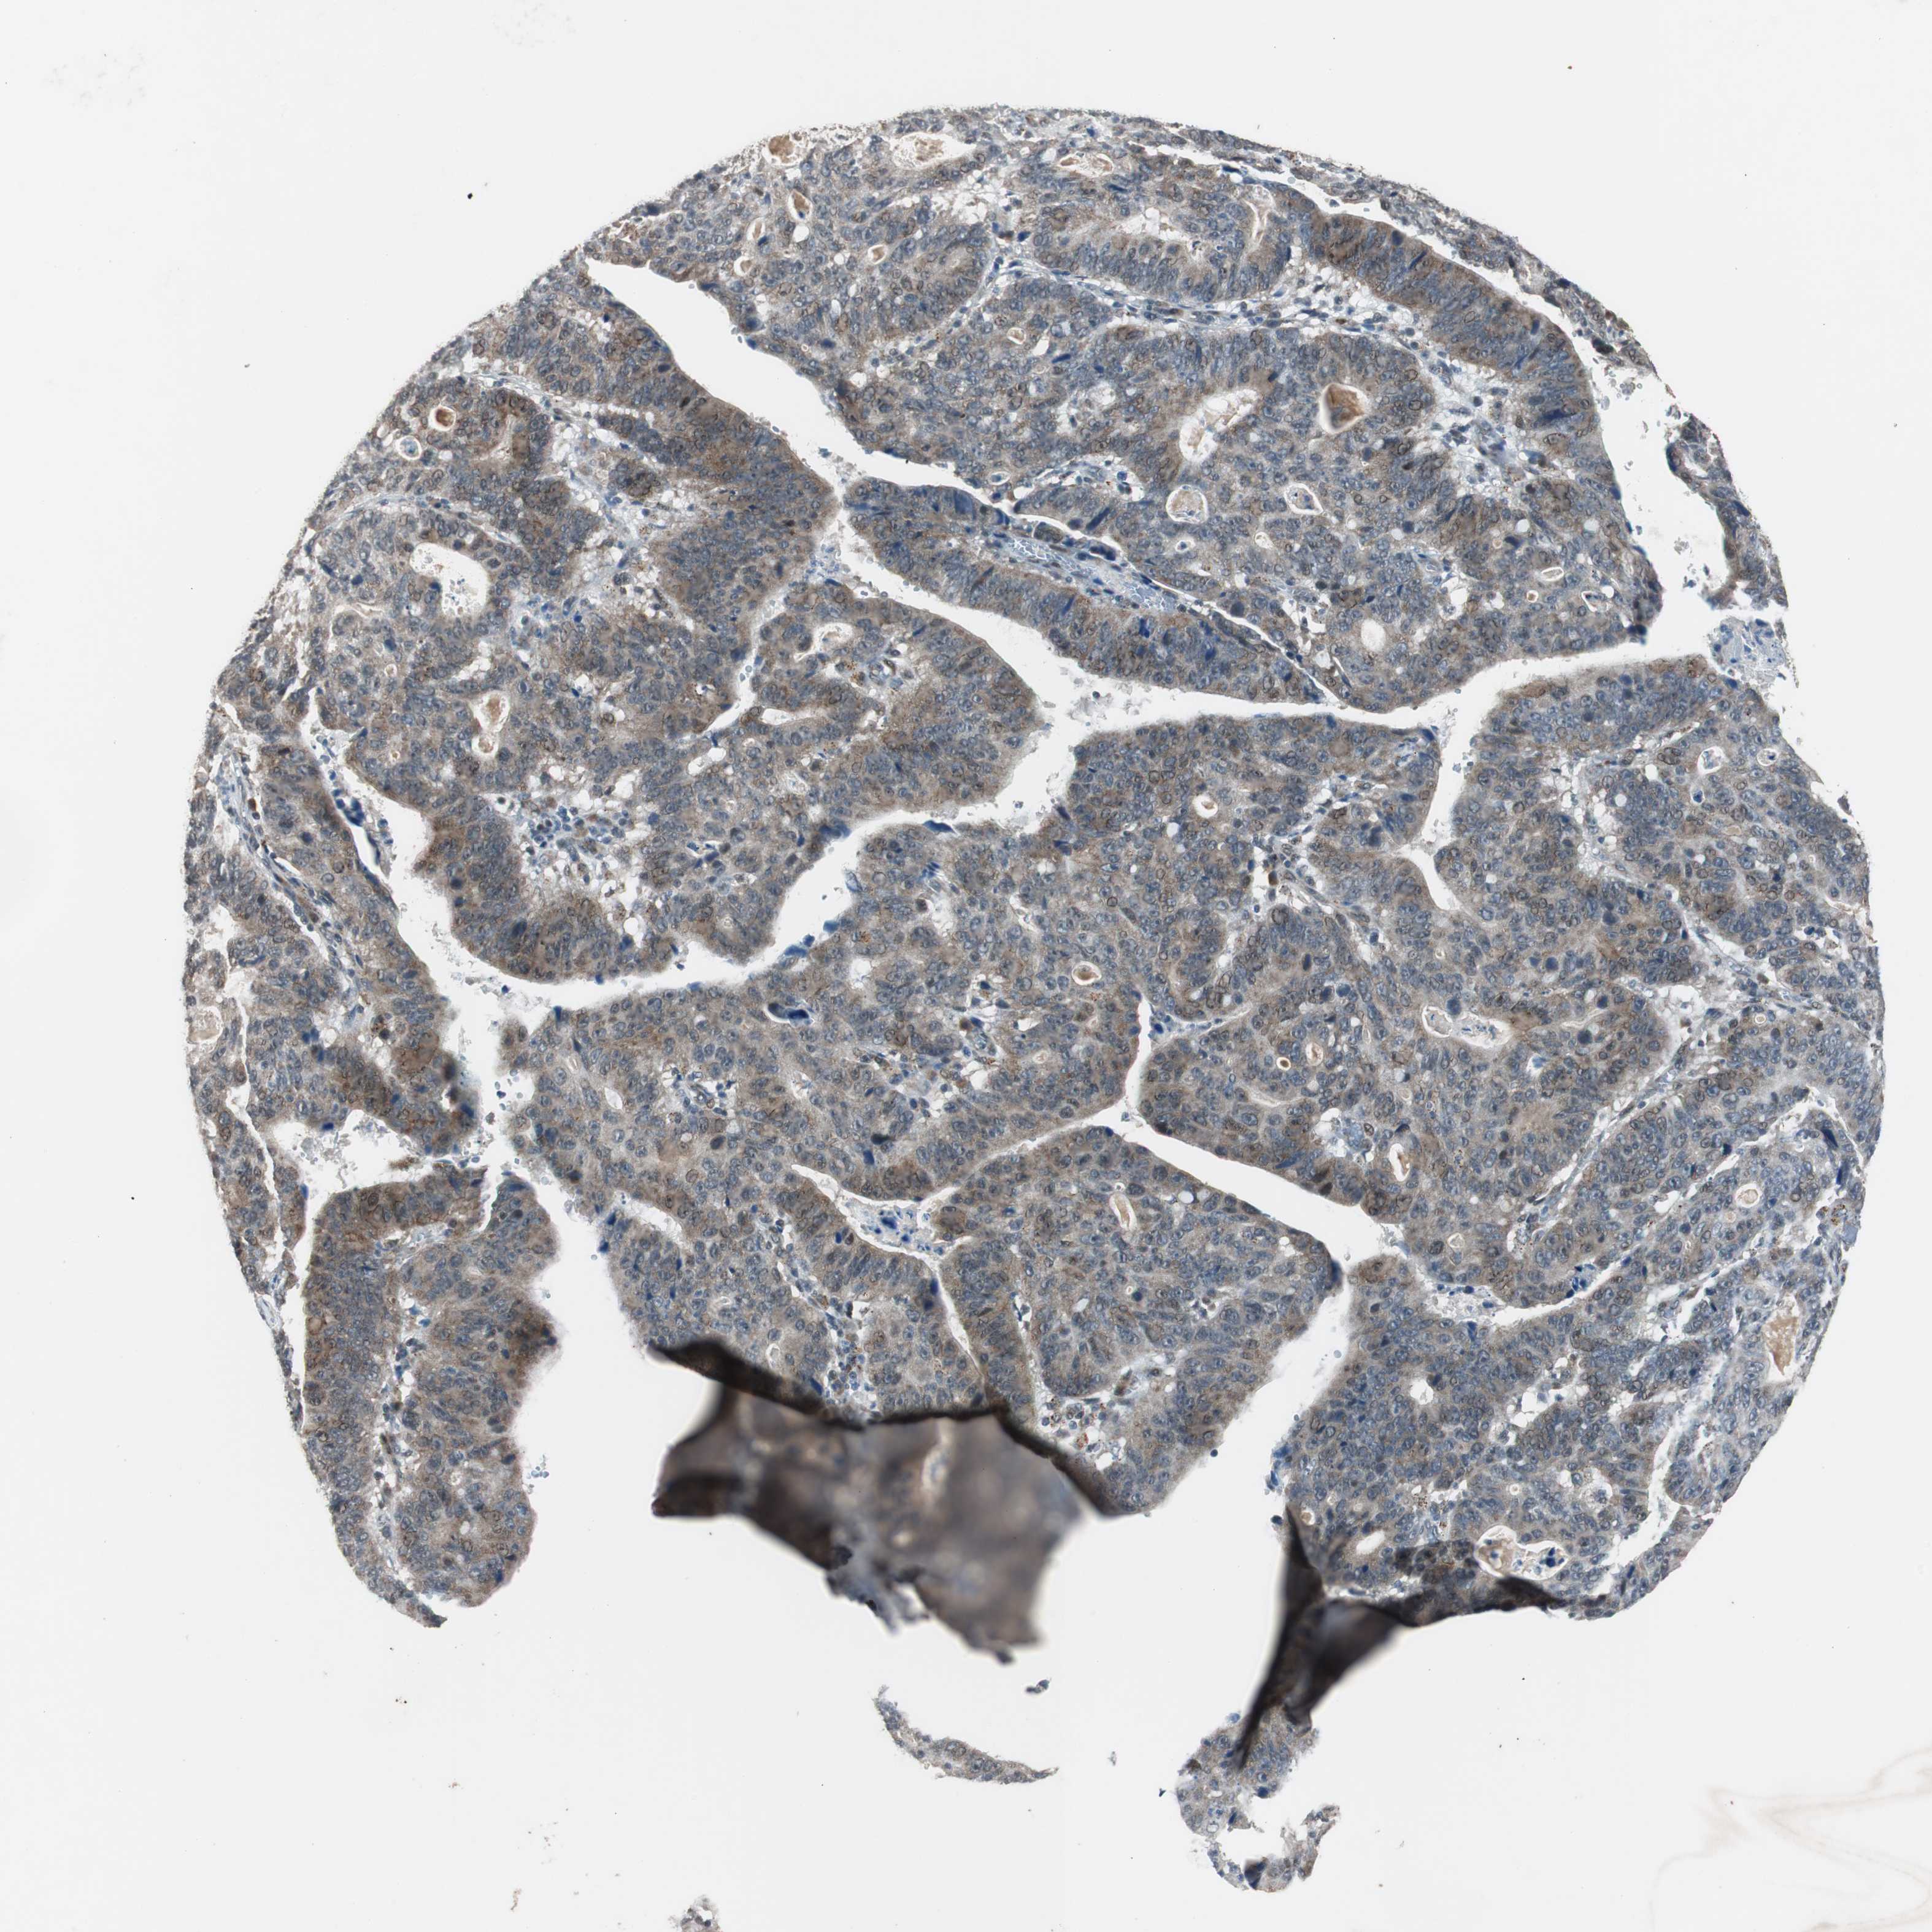

STOMACH CANCER - Protein expressioni

A mouse-over function shows sample information and annotation data. Click on an image to view it in a full screen mode. Samples can be filtered based on level of antibody staining by selecting one or several of the following categories: high, medium, low and not detected. The assay and annotation is described here.

Antibody stainingi

Antibody staining in the annotated cell types in the current human tissue is reported as not detected, low, medium, or high, based on conventional immunohistochemistry profiling in selected tissues. This score is based on the combination of the staining intensity and fraction of stained cells.

Each image is clickable and will lead to virtual microscopy that enables deeper exploration of all samples and also displays staining intensity scores, fraction scores and subcellular localization as well as patient and tissue information for each sample.

Antibody HPA007005

Staining

High

Medium

Low

Not detected

Intensity

Strong

Moderate

Weak

Negative

Quantity

>75%

75%-25%

<25%

None

Location

Nuclear

Cytoplasmic/membranous

Cytoplasmic/membranous,nuclear

Adenocarcinoma, NOS

Adenocarcinoma, High grade